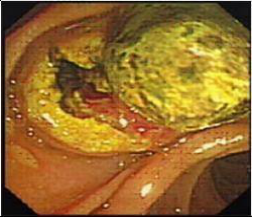

胆道疾病诊疗:主要以现代内镜外科为特色,通过微创手术的方法解决胆道疾病,利用十二指肠镜(治疗性ERCP)、胆道镜来完成的,大部分常见胆道疾病都是治疗性ERCP的适应证,如胆道结石、梗阻性黄疸、胆道蛔虫、胆道肿瘤、胆源性胰腺炎等。能极大避免胆道结石的残留与复发;同时,我科积累了上千例的腹腔镜胆囊切除(LC)的经验,还开展了腹腔镜肝叶切除、肝囊肿开窗引流、胆总管切开取石、胆道探查、胆总管切开I期缝合等手术,形成了自己的特色。对于晚期胆道肿瘤,通过胆道支架置入,提高了患者的生存质量;能早期解除胆源性胰腺炎的病因,降低了急性重症胰腺炎的死亡率。对复杂型肝胆管结石症、多发性肝内胆管结石采用手术中纤维胆道镜、超声定位、冲击波碎石等方法并用,对肝胆管结石进行彻底清除,大大减少了残石率及再发率。